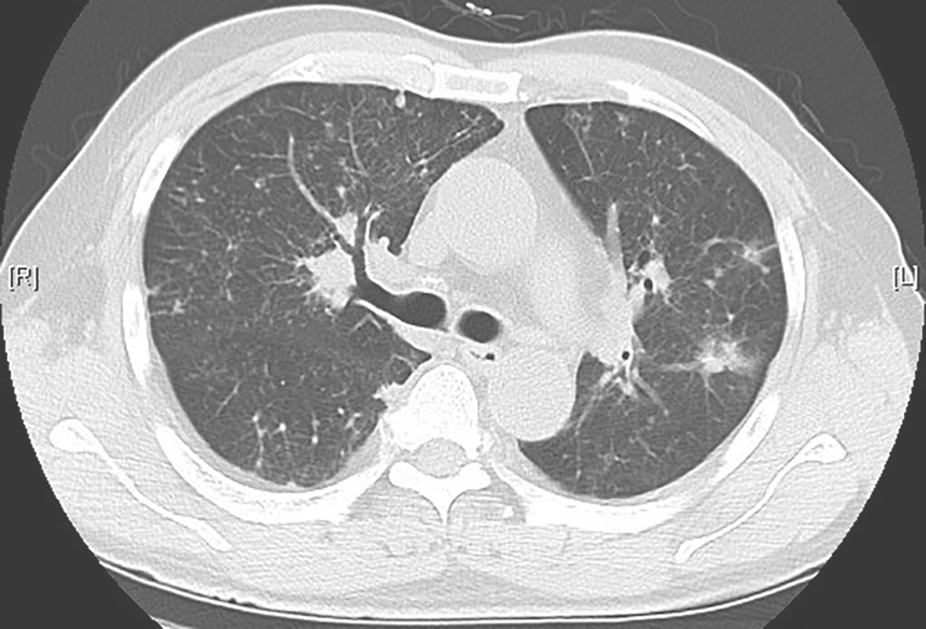

图3尘肺合并右侧气胸胸部CT表现

胸部CT可见双肺中上肺为主的高密度实变影,肺内结节影伴小叶间隔增厚,间隔旁肺气肿,右侧少量气胸,双侧胸膜肥厚